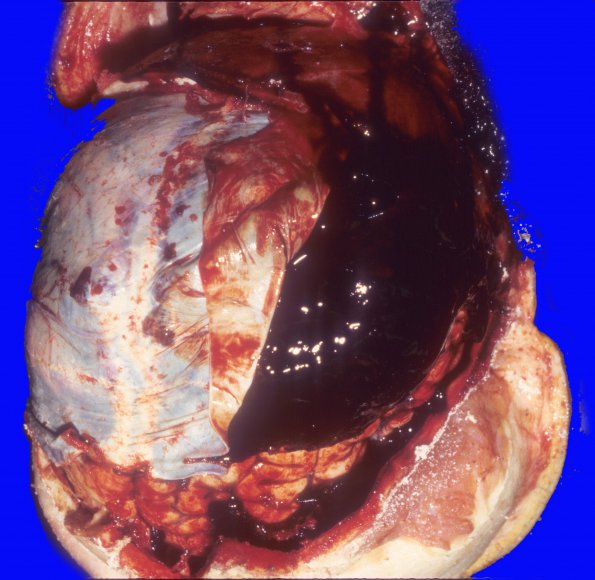

15A1 Hemorrhage, subdural (Case 15) 1

At autopsy there was a large, mostly acute, subdural hemorrhage.